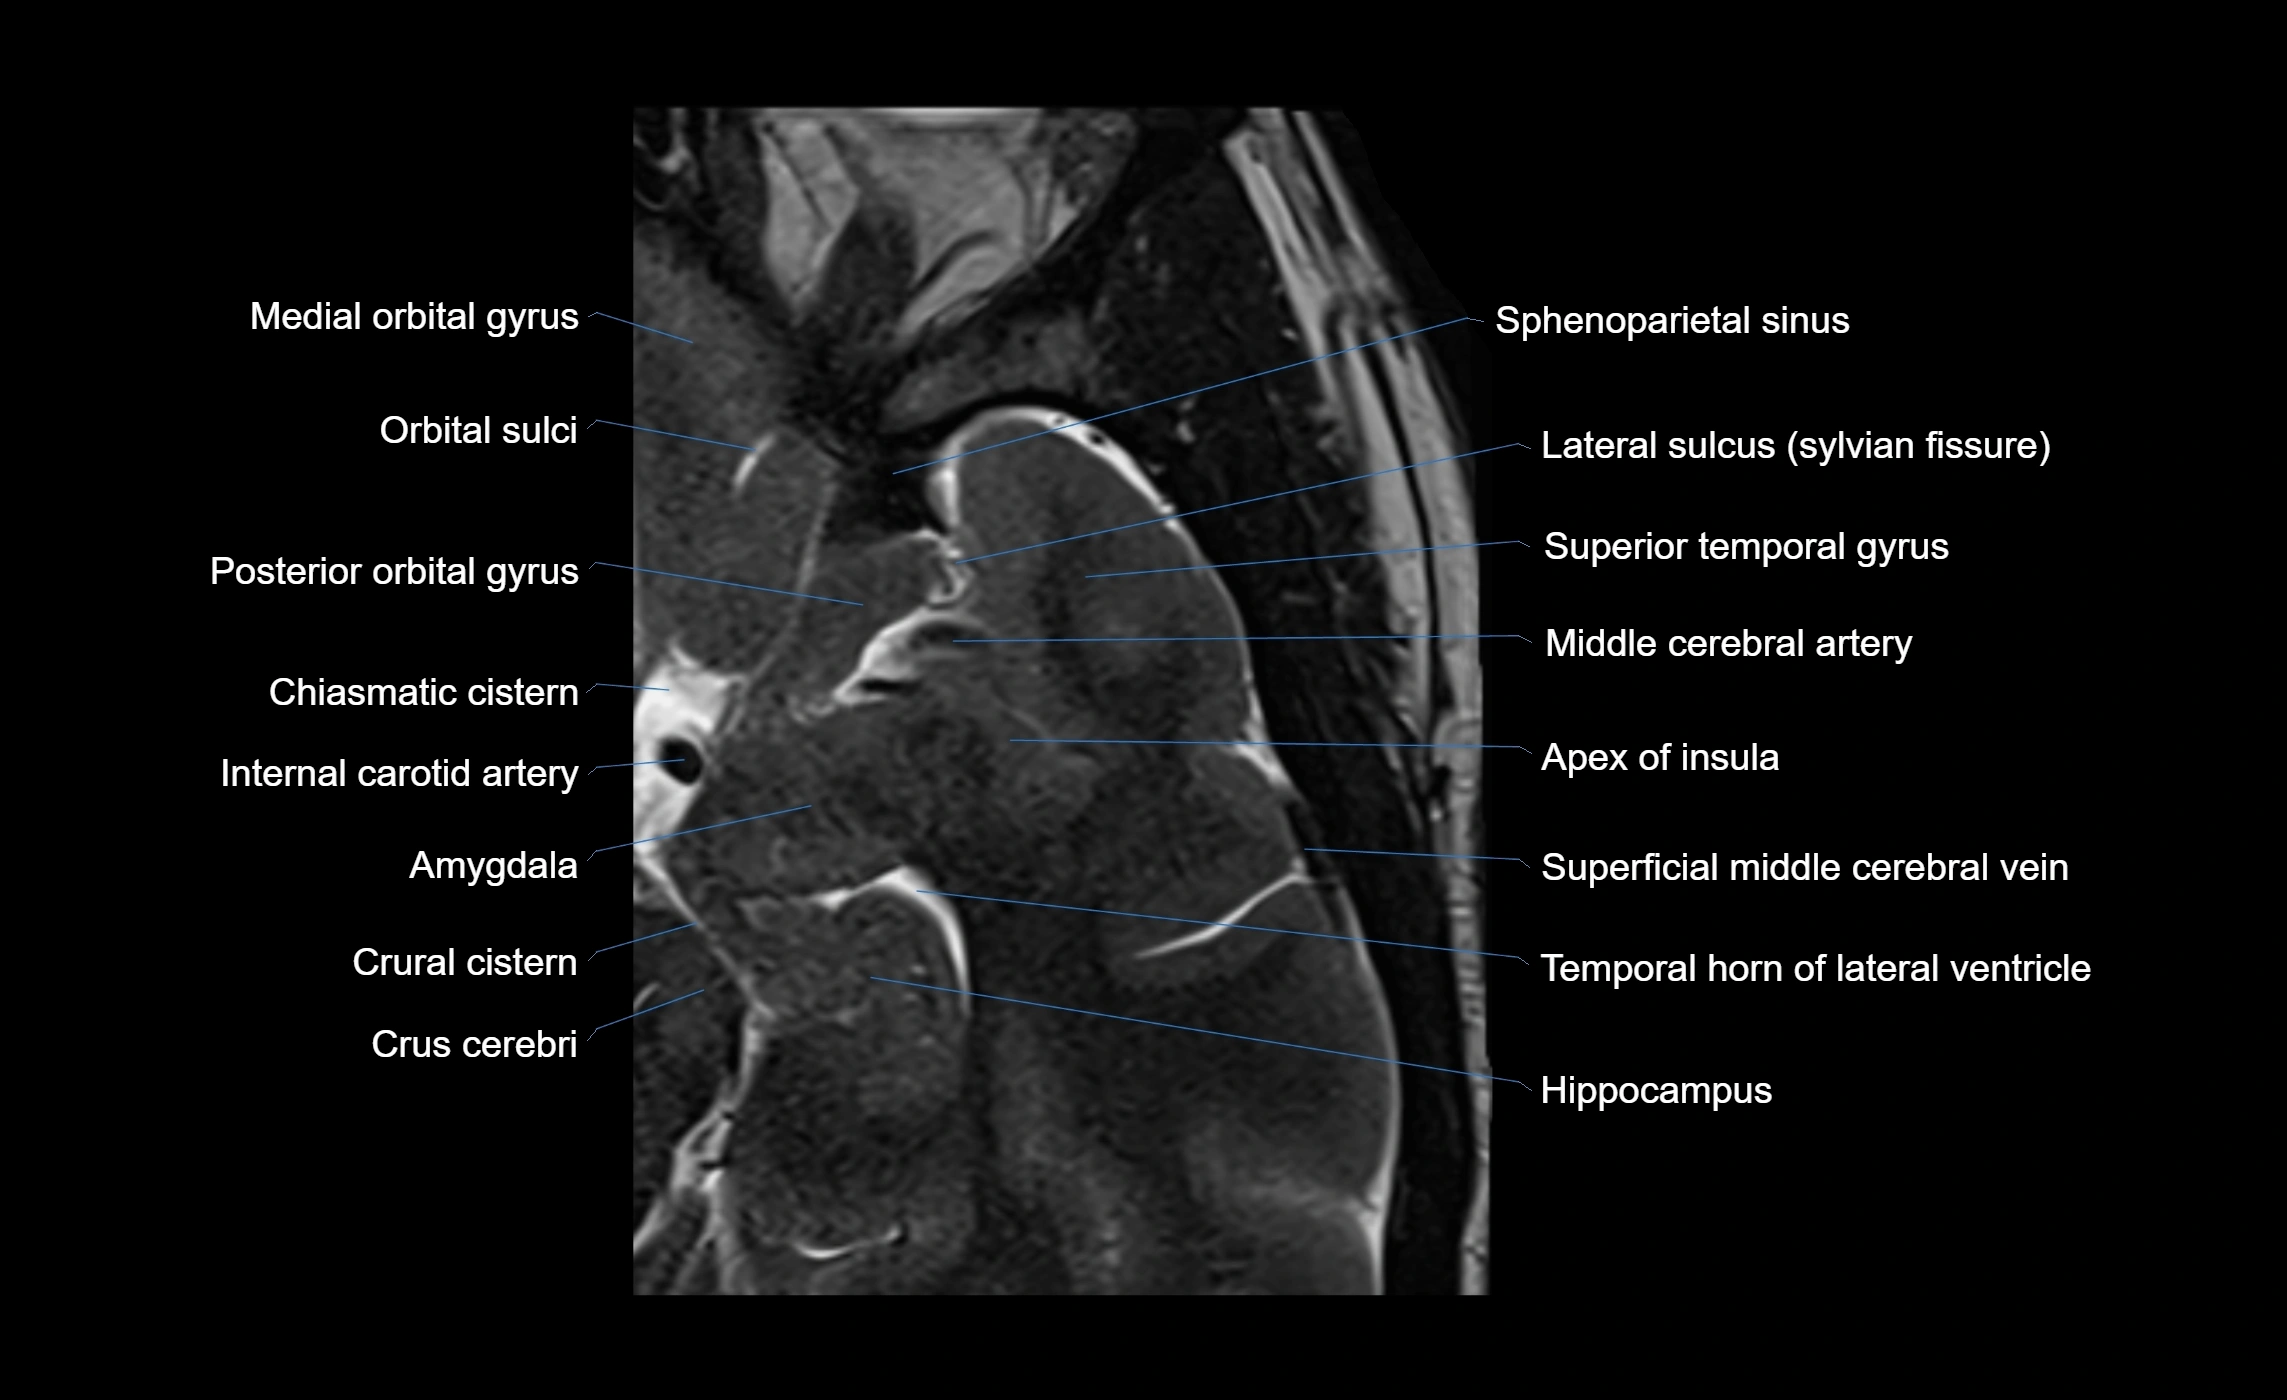

The anterior ascending ramus of the Sylvian fissure is a significant anatomical landmark in the lateral surface of the cerebral hemisphere. It represents one of the key branches of the Sylvian fissure (also known as the lateral sulcus) and plays an essential role in demarcating the boundaries between important cortical regions, notably within the frontal and parietal lobes. Understanding its anatomy and imaging appearance is crucial in neuroradiology, neurosurgery, and neuroanatomy for accurate localization and identification of adjacent brain structures.

• The anterior ascending ramus is a short, superiorly oriented branch that arises from the main stem of the Sylvian fissure.

• It projects upward (anteriorly and slightly dorsally) from the lateral sulcus into the inferior frontal gyrus.

• This ramus separates the pars opercularis (opercular part) from the pars triangularis (triangular part) of the inferior frontal gyrus.

• The anterior ascending ramus marks the boundary between Broca's area and adjacent cortical areas in the dominant hemisphere.

• T1-weighted imaging:

• The Sylvian fissure and its anterior ascending ramus appear as low-signal intensity (dark) CSF-filled clefts between the gyri.

• Clear demarcation between adjacent gray and white matter.

• T2-weighted imaging:

• The fissure, including the anterior ascending ramus, is hyperintense (bright) due to CSF signal.

• Better visualization of the separation between opercular and triangular parts of the inferior frontal gyrus.